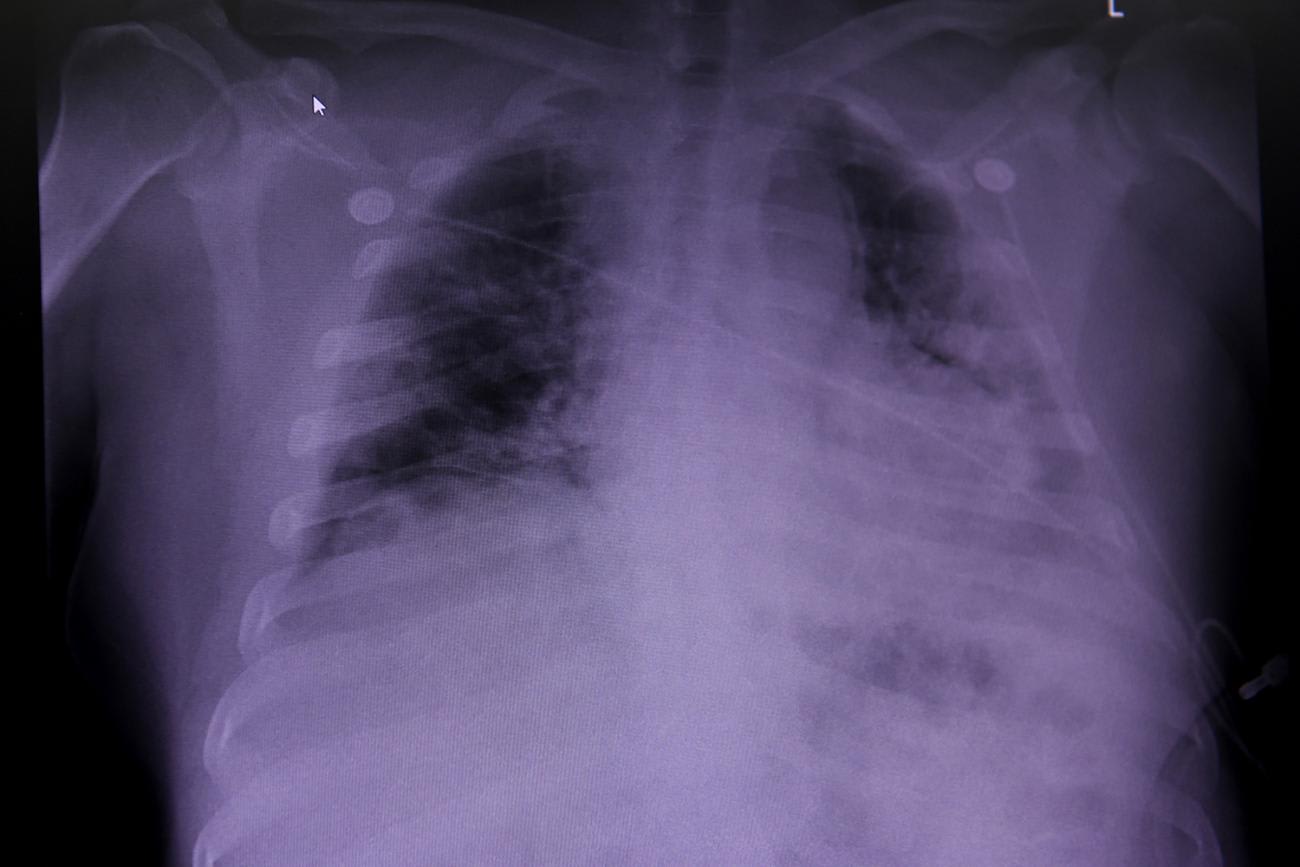

A recent study found that people with obesity and COVID-19 were 113 percent more likely to be hospitalized and 48 percent more likely to die. The U.S. Centers for Disease Control and Prevention (CDC) announced in early October that even individuals who are overweight may be at greater risk of developing severe COVID-19 infection. Obesity and overweight appear to put people at greater risk of dying from COVID-19 by weakening the immune system, decreasing the functioning of the lungs, and contributing to higher inflammation. There is also concern that a vaccine against COVID-19 may not work as well in people who are obese.